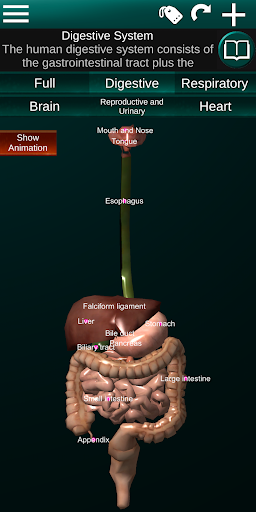

Internal Organs in 3D Anatomy لـ Vodafone Smart N9 Lite

(الأجهزة الداخلية في)

يمكنك هنا تنزيل ملف حزمة تطبيق أندرويد "Internal Organs 3D Anatomy" الخاصة بجهازVodafone Smart N9 Lite مجانًا، نسخة ملف حزمة تطبيق أندرويد - 3.4 للتحميل على Vodafone Smart N9 Lite اضغط ببساطة على هذا الزر. إنه سهل وآمن. نحن نقدم فقط ملفات حزمة تطبيق أندرويد الأصلية. إذا انتهكت أية مواد موجودة في الموقع حقوقك قم بإبلاغنا من خلال